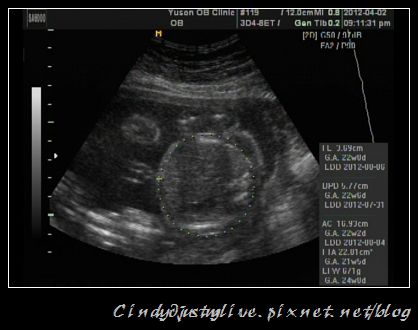

這次的測量預估是671克

後來回家算了算是還好啦,20-24週應該要是600-750克,那我22週671克應該不算太大,我有點怕小孩太大會不好生,尤其之前電視上柯以柔跟那個粉豬老是在講他們的生產經,嚇我嚇的要命!